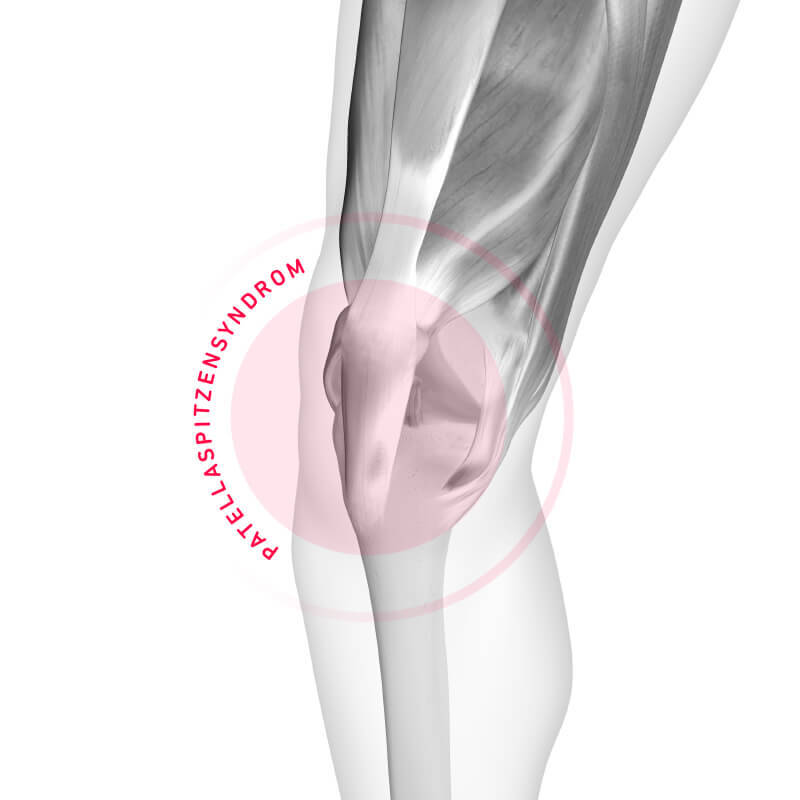

Diagnose: Patellaspitzensyndrom

Symptome, Ursachen und Therapie

Die Patella ist eine Sehne, die über die Kniescheibe verläuft und den Oberschenkelmuskel mit dem Schienbein verbindet. Sobald das Kniegelenk sich bewegt, wird die Patellasehne beansprucht – sie muss also einiges aushalten. Bei einer andauernden Überbelastung wird es irgendwann zu viel, und es kommt zu einer Reizung der Patellasehne. Wenn die Reizung nicht nach kurzer Zeit von allein verschwindet und chronisch wird, können sich durch Verschleiß bedingte sogenannte „degenerative“ Veränderungen entwickeln und man hat es mit einem Patellaspitzensyndrom zu tun.

Bei Volleyballern oder Basketballern sind es die schnellen Start- und Stoppbewegungen, plötzliche Richtungswechsel und Sprünge, die der Patellasehne ganz schön zusetzen – daher auch der Name „Jumper’s Knee“. Auch das Laufen besteht genau genommen aus vielen kleinen Sprüngen. Daher sind auch Läufer nicht davor gefeit: Wenn das Knie etwa regelmäßig durch Fehlbelastung beim Laufen zu stark beansprucht wird, kann es ebenfalls zu einer Reizung der Patellasehne kommen. Vielleicht bist Du zu enthusiastisch ans Training heran gegangen und hast im Flow Deine Kräfte überschätzt; vielleicht bist Du aber auch zu lange im hügeligen Gelände unterwegs gewesen oder lange und häufig auf sehr hartem Untergrund wie Asphalt gelaufen. Inspiziere auch Deine Laufschuhe – wenn sie nicht mehr in Ordnung sind, können sie ihre Funktion nicht mehr ausreichend erfüllen und gehören ausgetauscht.

Besondere Vorsicht ist geboten, wenn bei Dir bereits eine verminderte Dehnbarkeit der Patellasehne, ein Kniescheibenhochstand (Patella alta) oder eine angeborene Bänderschwäche diagnostiziert wurde; in diesen Fällen bist Du ebenfalls anfällig für das Patellaspitzensyndrom.

Symptome: Woran erkenne ich ein Patellaspitzensyndrom?

Die Entzündung der Patellasehne macht sich durch Schmerzen an und unterhalb der Kniescheibe bemerkbar. Es ist unbedingt ratsam, dass Du von Deiner Ärztin*Deinem Arzt abklären lässt, ob es sich tatsächlich um ein Patellaspitzensyndrom handelt – oder die Schmerzen einen anderen Ursprung haben. Auf die leichte Schulter solltest Du Knieschmerzen jedenfalls nicht nehmen. Wenn Du eine gereizte Patellasehne ignorierst und Dein Knie weiter stark beanspruchst, kann dies sogar zu einem Riss oder Teilriss der Sehne führen.